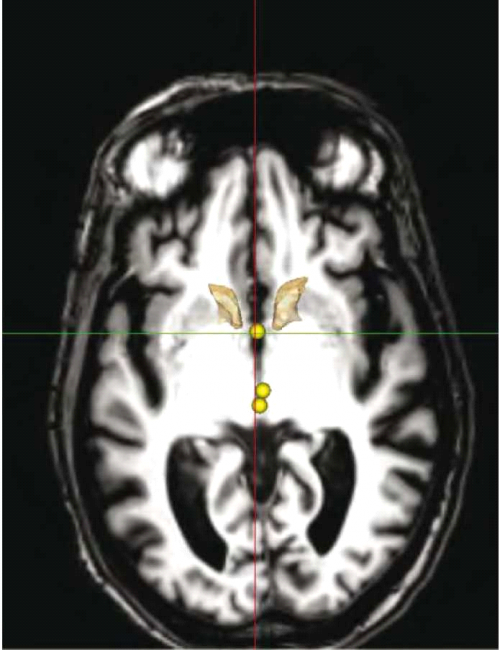

ההליך הניתוחי להשתלת קוצב לגירוי מוח עמוק בחולי אלצהיימר, דומה לזה המבוצע ביתר ההתוויות, כגון הפרעות תנועה, כאב כרוני והפרעות נפשיות, ומבוצע בשני שלבים: בשלב הראשון מושתלים הקוצבים המוחיים. ראשית, עוברים החולים הדמיה מוחית בתהודה מגנטית (Magnetic Resonance Imaging, MRI) (ראו איור 1) על מנת לשלול פתולוגיה העלולה לסכן את החולה במהלך הניתוח, כמו מפרצת (Aneurysm) מוחית, עיוות (Malformation) בכלי הדם או גידול. ביום הניתוח מונחת על ראש החולה מסגרת Stereotactic ובהמשך מבוצעת טומוגרפיה ממוחשבת (CT ,Computer Tomography) של המוח עם המסגרת (ראו איור 2). בגוף המסגרת ה-Stereotactic קיימים סמנים קבועים המהווים נקודות יחוס ומאפשרים למעשה להלביש את תמונת ה-MRI על גבי תמונת ה-CT. מהלך הניתוח מבוצע בערות מלאה של המטופל, ומתחיל בקידוח חור קטן בגולגולת דרכו תוחדרנה האלקטרודות למוח. השתל יוחדר תמיד קדמית לקליפת המוח האחראית על תנועה (Motor cortex). לאחר קדיחת החור, מוחדרות אלקטרודות למוח שתפקידן לבצע רישום מוחי אלקטרופיזיולוגי. רישום זה נותן לצוות המנתח התוויה בנוגע למיקום האלקטרודה, בעזרת זיהוי דפוסי הפעילות המאפיינים את אתרי המוח השונים ומהווים מעין חותמת שלהם. לאחר מיקום האלקטרודה בגרעין העמוק, מבוצע גירוי-מבחן במסגרתו מתבקש המטופל לבצע מטלות התנהגותיות המאתגרות את התפקוד הפגוע, כמו זיכרון בחולי אלצהיימר או רעד בלוקים בהפרעות תנועה. מטרת הבדיקה ההתנהגותית היא לוודא את מיקומה של האלקטרודה ולשלול תופעות לוואי מהגירוי, שיחייבו מיקום מחדש של האלקטרודה. הליך זה מבוצע בשני צדי המוח.